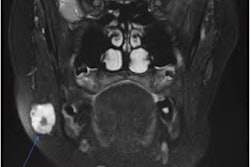

Imaging revealed a 1 x 0.9 cm metallic density in the man's appendix, as well as inflammatory findings consistent with acute appendicitis. Imaging also showed a lack of normal muscle contractions in the intestines in the man's regional right lower quadrant, the authors wrote.

An abdominal x-ray revealed a 1 x 0.9 cm metallic density, which ended up being a dental crown, in the appendix near its origin in the cecum. Images courtesy of Brennan et al. Licensed by CC BY 4.0.